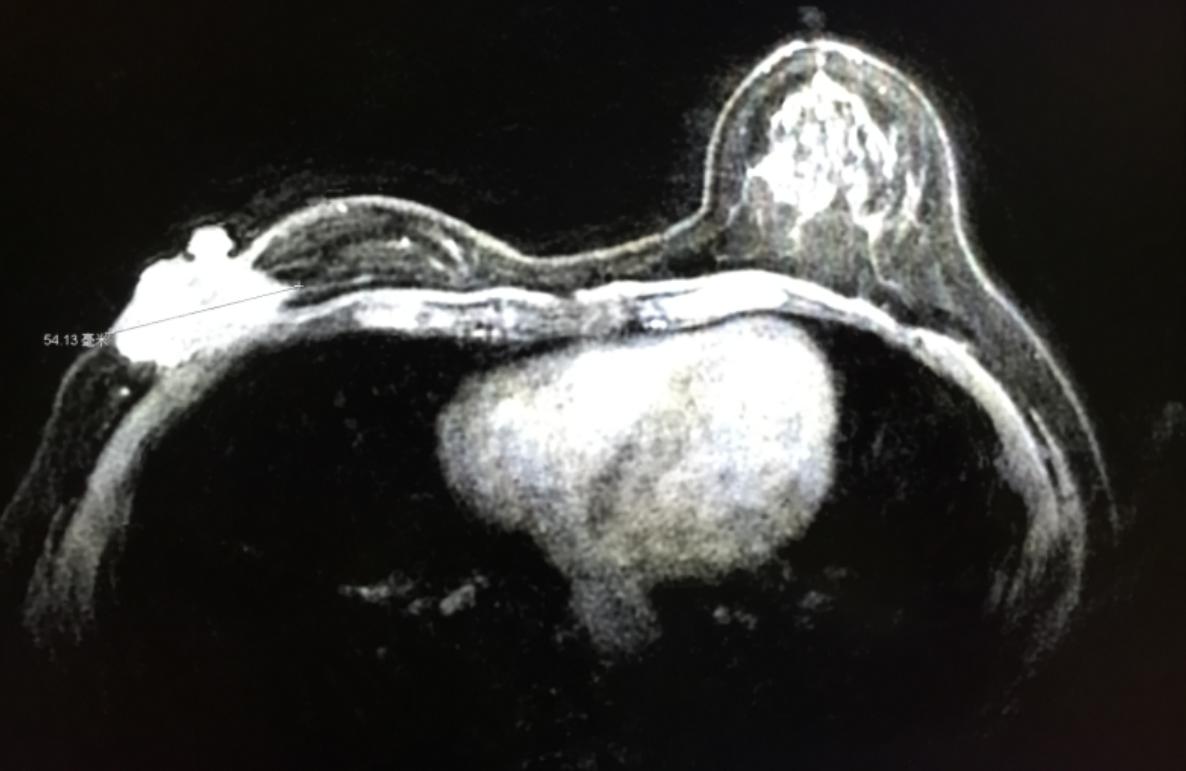

图2:乳腺MRI

患者,女性,48岁,已绝经。右乳浸润性导管癌T4N1M1(骨转移)。

体检:右乳可见明显隆起,表面菜花样赘生物,橘皮征(+),乳透凹陷(+),右乳可触及肿块8 cm,质硬、压痛、固定。

2014年4月右乳肿块约8.0*4.4 cm,CA153:147;CEA:128

2015年6月右乳肿块约5.4*2.8 cm,CA153:60;CEA:19